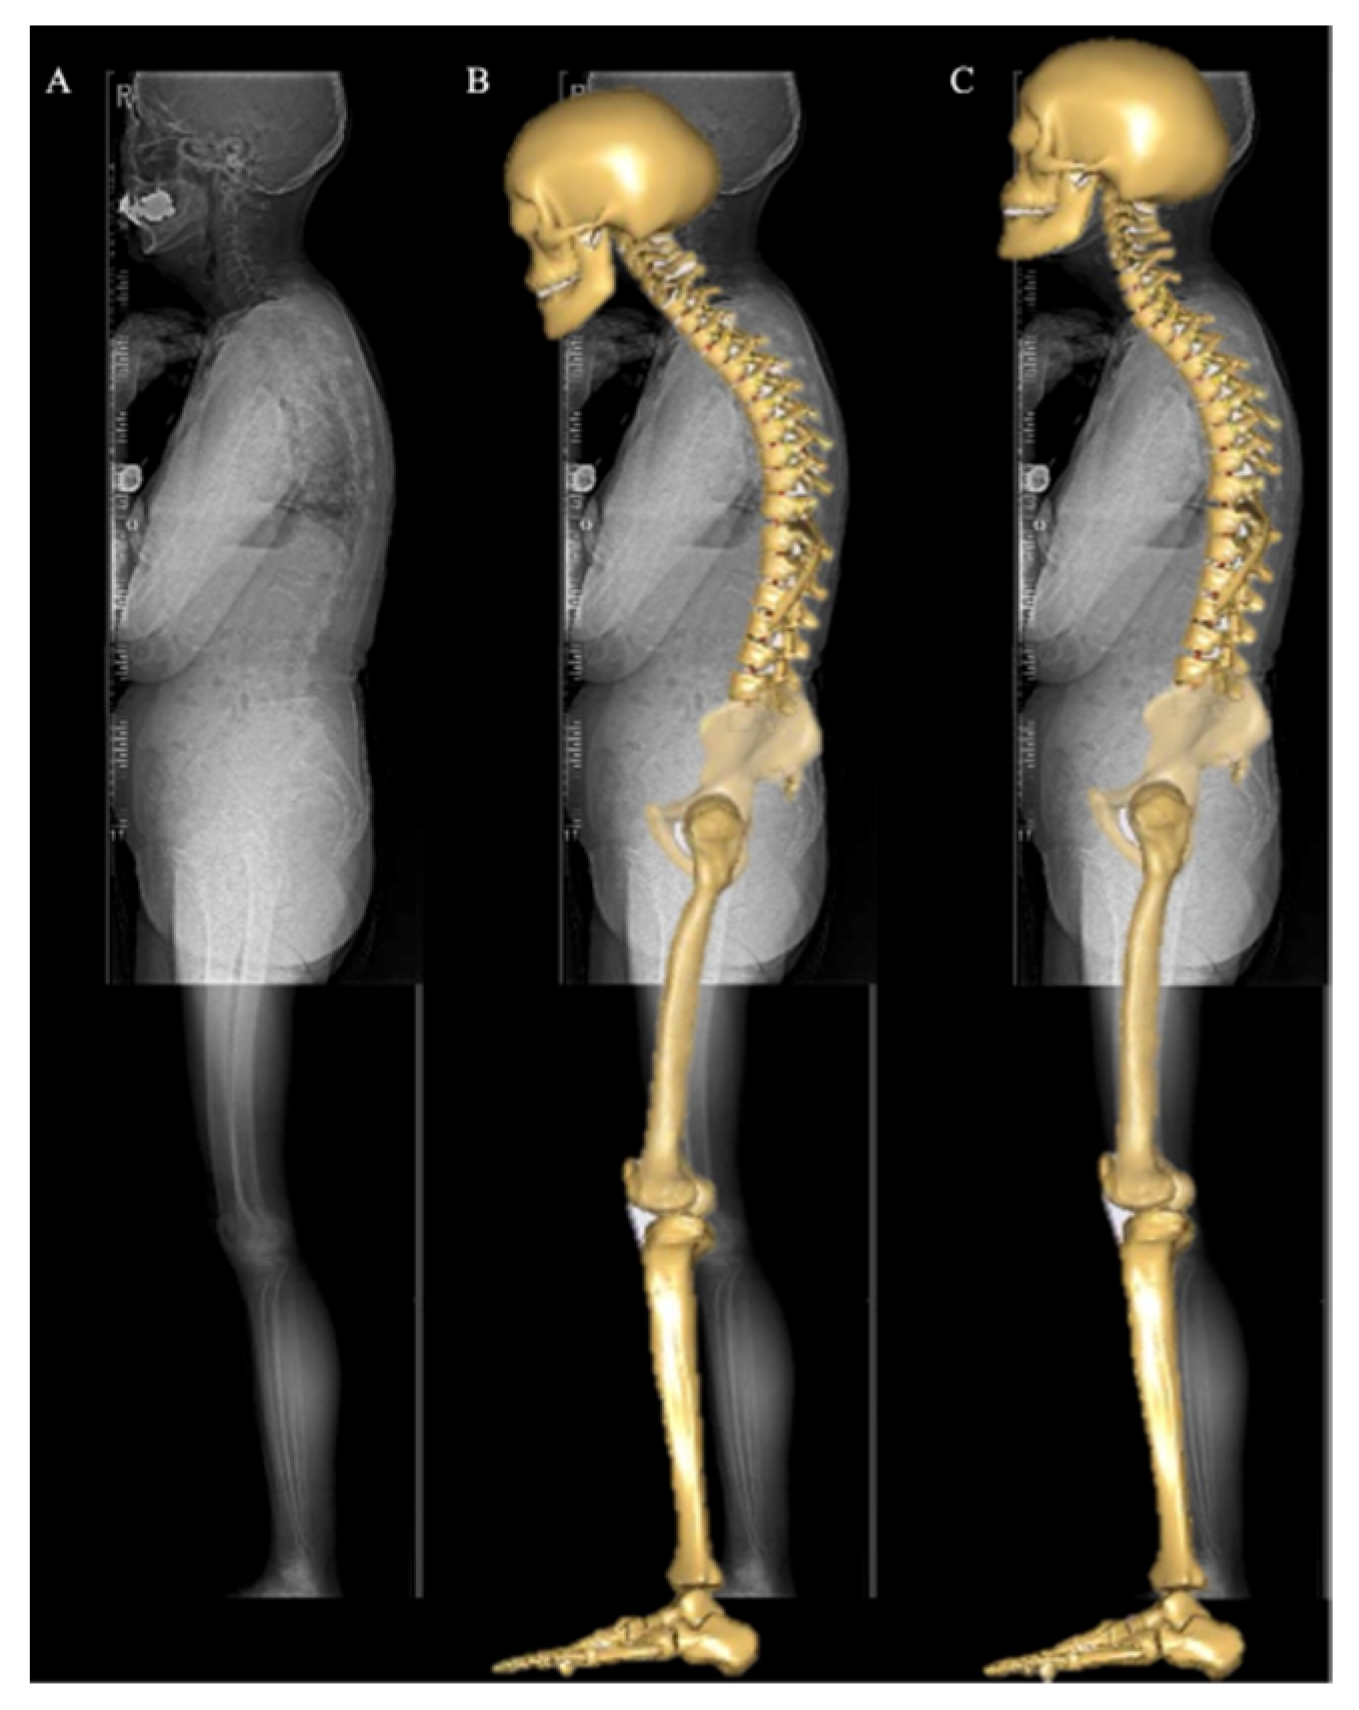

2.3. Musculoskeletal Model

2.4. Spinopelvic and Lower-Extremity Sagittal Alignment Input and Simulation Process